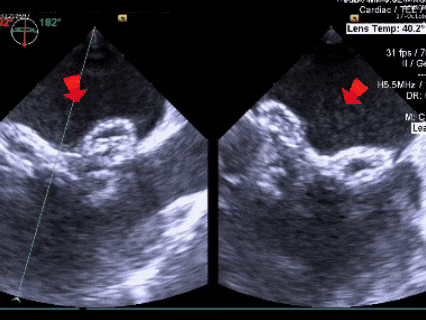

锁定后,封堵器形态良好,进行牵拉试验,

超声下可见封堵器整体移动,右盘面未被拉开

锁定后评估

彩色多普勒血流成像显示无残余分流存在